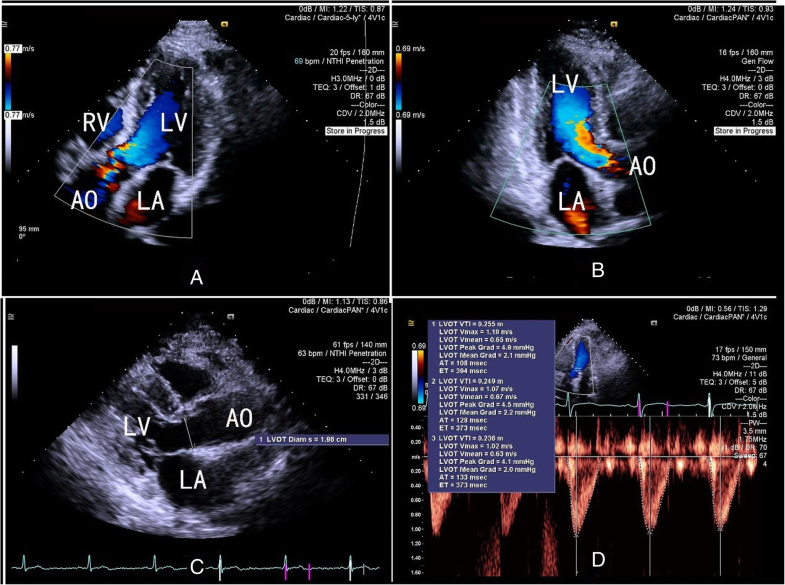

Color Doppler echocardiograms of a patient who showed a large increase What Do Colors Mean In Echocardiogram To aid observation of turbulent flow there is a. Echocardiogram an echocardiogram uses sound waves to show how blood flows through the heart and heart valves. With color doppler, different colors are used to designate the direction and quantity of blood flow. Traditionally, flow towards the transducer is red, flow away from the transducer is blue, and higher velocities are. What Do Colors Mean In Echocardiogram.